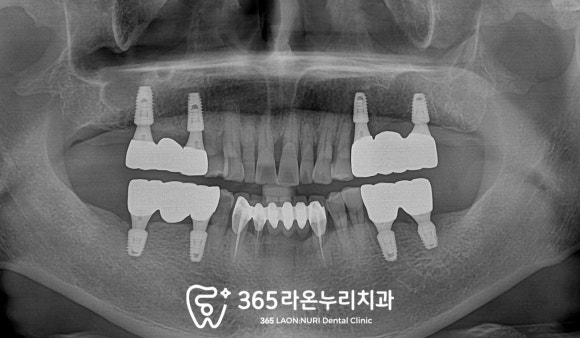

■ 5. 최종 보철물 제작 및 체결

치료가 마무리된 모습을 보겠습니다.

픽스처 식립 개수는 최소로 하면서

구치부 기능은 모두 회복되었습니다.

또한 임시치아를 사용하며

적응할 시간도 충분히 가지셨기에

최종 보철이 올라갔음에도

여전히 편안하게 받아들이셨답니다.

최근에 정기검진을 오셔서

엑스레이를 찍어 살펴보니

관리도 잘되고 있으셨습니다.

환자께서도 불편감 없이 잘 사용 중이라며